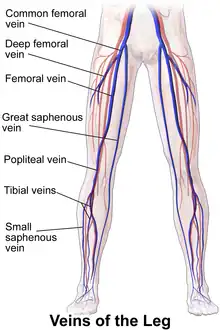

Veins

The veins are subdivided into three systems. The deep veins return approximately 85 percent of the blood and the superficial veins approximately 15 percent. A series of perforator veins interconnect the superficial and deep systems. In the standing posture, the veins of the leg have to handle an exceptional load as they act against gravity when they return the blood to the heart. The venous valves assist in maintaining the superficial to deep direction of the blood flow.[44]

Superficial veins:

Deep veins:

- Femoral vein, whose segment is the common femoral vein

- Popliteal vein

- Anterior tibial vein

- Posterior tibial vein

- Fibular vein